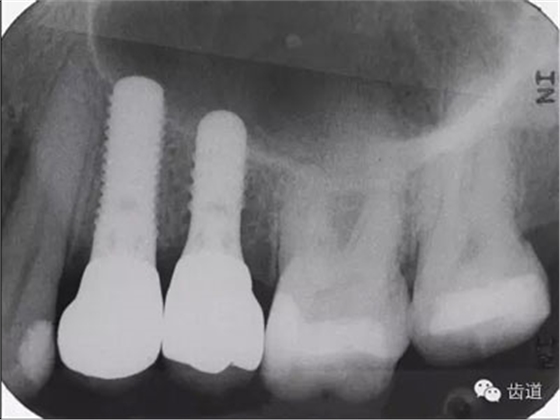

VF軟件也可以記錄上下頜之間的咬合關系,這對于將模型精確的上HE架很重要,所以對于復雜的種植病例(圖15),VF軟件也可以勝任將HE關系轉移至HE架的工作。HE架上的模型位置精確,種植體植入的位置和角度才能準確(圖16)。

圖15:種植病例

圖16:種植體X片